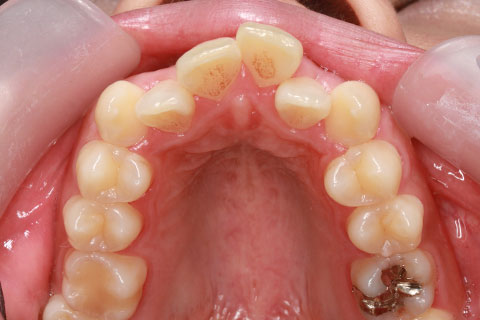

矯正期間18ヶ月

ハーフリンガル矯正2(上の歯のみ舌側矯正で治療)

治療前

治療中

治療後

- 年齢・性別

- 23歳女性

- 治療期間

- 1年6ヶ月

- 抜歯

- 上顎4番

- 治療費

- 110万円(税込み)

- 備考

- ハーフリンガル矯正

- 治療内容

- 上下前歯部凸凹の改善

- 施術の副作用(リスク)

- 裏側矯正の特性上、表側矯正と比較すると治療期間が長くかかる場合が多い。